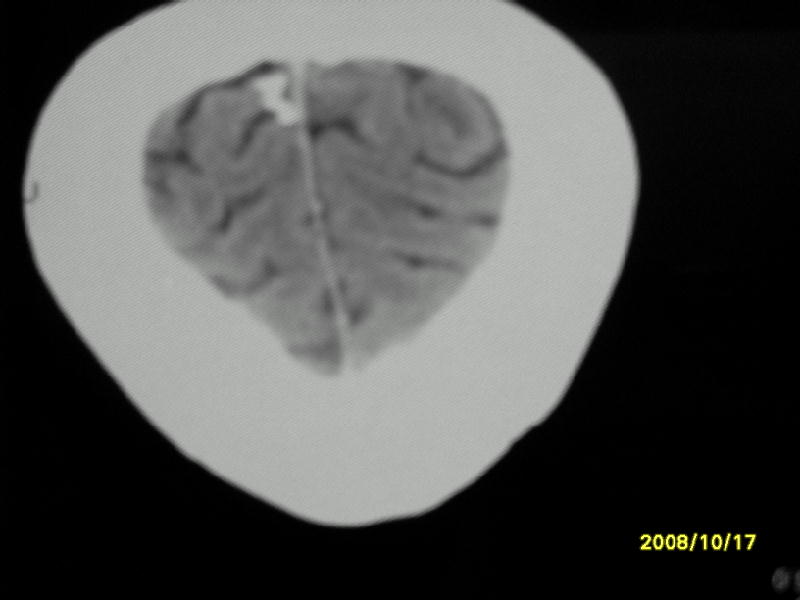

检查名称:     ct颅脑平扫           男     28岁

表现:左顶叶见斑点状致密影。边缘清,大小约0。3*1。0cm,余脑实质密度及灰白质结构示见异常。脑室系统大小,形态,密度未见异常。脑沟。脑裂。脑池未见异常密度影。中线结构无移位。

印象:左顶叶少许钙化灶

左顶叶见斑点状致密影。边缘清,大小约0。3*1。0cm,余脑实质密度及灰白质结构示见异常。脑室系统大小,形态,密度未见异常。脑沟。脑裂。脑池未见异常密度影。中线结构无移位。

印象:左顶叶少许钙化灶。

镰旁钙化

镰旁钙化或顶骨内板骨嵴部分容积效应,建议mri矢状位扫描观察与顶骨的关系。排外后者。